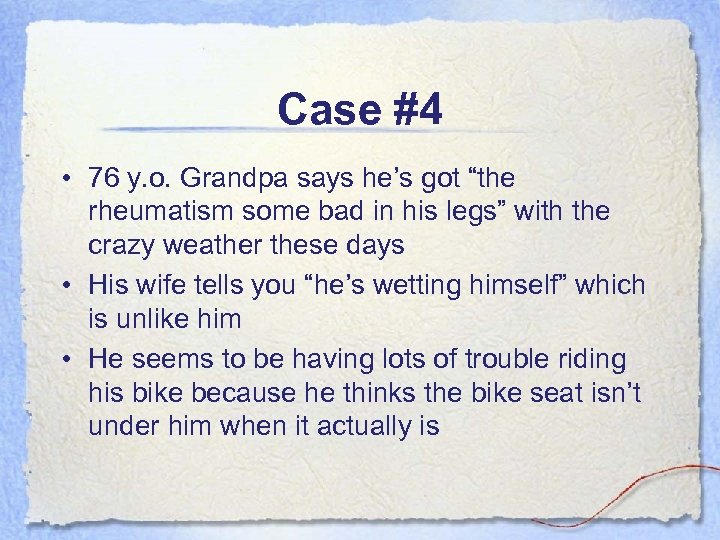

Case #4 • 76 y. o. Grandpa says he’s got “the rheumatism some bad in his legs” with the crazy weather these days • His wife tells you “he’s wetting himself” which is unlike him • He seems to be having lots of trouble riding his bike because he thinks the bike seat isn’t under him when it actually is

Case #4 • 76 y. o. Grandpa says he’s got “the rheumatism some bad in his legs” with the crazy weather these days • His wife tells you “he’s wetting himself” which is unlike him • He seems to be having lots of trouble riding his bike because he thinks the bike seat isn’t under him when it actually is